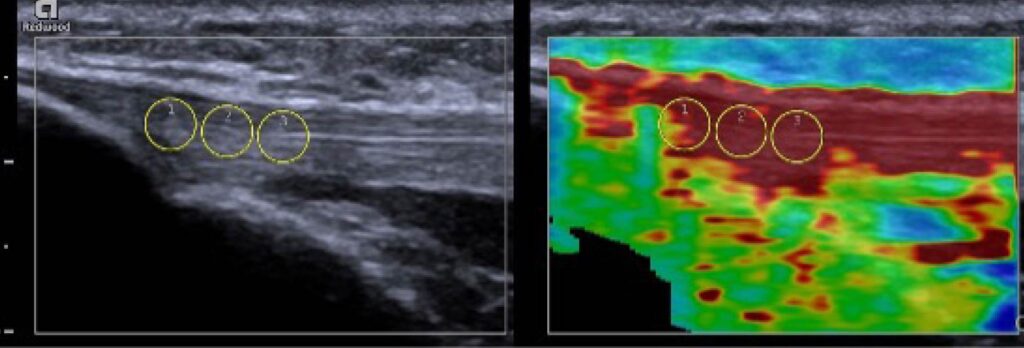

Figure 3: B-mode image of the patellar tendon (left) and an elastogram of the same region of interest (right). On the elastogram, areas of increased stiffness are indicted by dark red. Specific regions of interest can be assessed and quantified, demonstrated by the three diameter circles, which can provide different shear velocities for each region.

Compression elastography (CE) is characterized by the application of repeated manual compression on tissues by utilizing a hand-held US transducer to reproduce tissue displacements, or strain on the tendon, to exhibit relative elasticity.15 Using rhythmic and regular compressions of the area, the evaluator is able to target a specific area of interest to observe qualitative strain on the tissue. These strains are collected, and a specialized software is used to display a color-coded elastogram, typically displayed next to the conventional ultrasound image on the screen. In the color-coded elastogram, red frequently indicates soft (high-strain), blue indicates hard (low-strain), green and yellow indicate intermediate stiffness (medium-strain).16 More deformation is observable in softer tissues, which then experience larger strain than stiffer tissues which experience lesser strain.15 Successful and accurate measurements with CE depend on the depth of the targeted tissues and probe position, which make this technique more difficult to execute and operator-dependent.17 If the stress distribution within the tissue is not uniform or standardized during CE, this can affect the Young’s elastic modulus measurement that describes the elasticity of the tissue.15

Shear-wave elastography (SWE) can also be utilized to characterize absolute tissue elasticity of soft tissues. SWE involves a perpendicular stress applied to the tissue which produces shear-waves. These waves are then measured with radiofrequency images to create a colored tissue displacement map that is used to calculate shear-wave velocity and shear modulus.17 Thus, we are allowed to assess the elastogram to evaluate the tendon tissue for elasticity in a more objective way compared to CE since there is no repeated manual compression utilized in this technique. The displacement will display different colors as noted above: red typically defines hard tissue consistency, blue as soft consistency, and green and yellow as in-between. Modifications on tissue elasticity can potentially be detected earlier than observable deformities with conventional ultrasound images most often termed B-mode images in the literature (Figure 3).15 Studies that investigated SWE demonstrated increased stiffness in symptomatic tendons and increased stiffness in the proximal and mid-patellar region.21,22